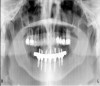

There are several ways to diagnose periodontitis. In addition to soft tissue evaluation, one of the most common and accurate methods is to use a periodontal probe in affected areas and record probing depths. Bleeding on probing is another indication of unhealthy periondontal tissues. Radiographs can be used, but they have limitations in initial diagnosis because bone loss is typically associated with severe and chronic periodontal disease; therefore, radiographs are better used to confirm diagnosis. However, vertical bitewings taken over time can be placed side-by-side to detect even slight differences in contrast.